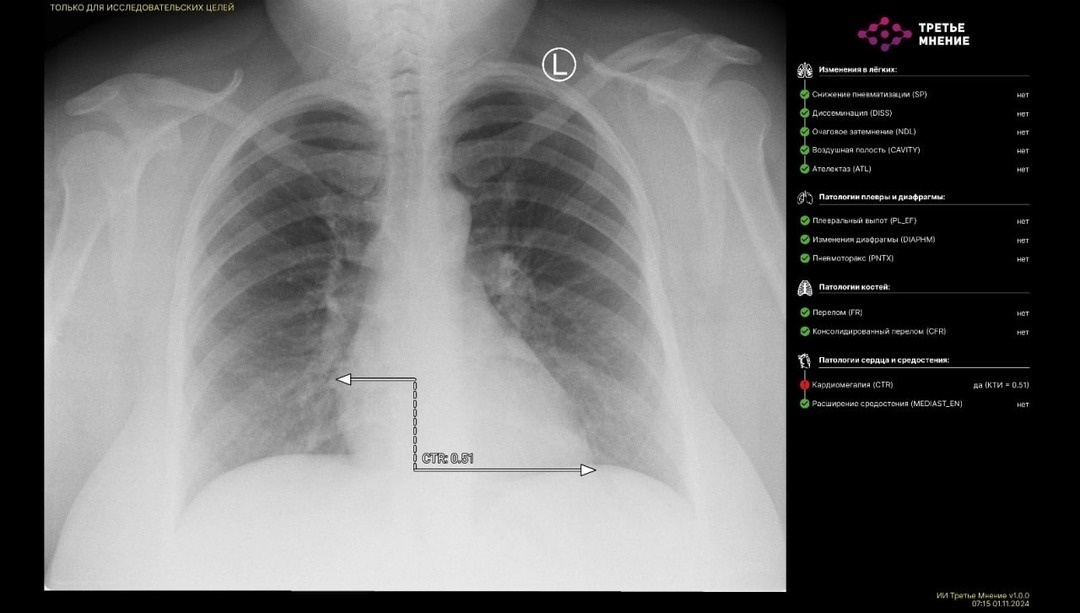

Кабинет флюорографии находится в поликлинике Караидельской ЦРБ. Направление можно взять у фельдшера или врача-терапевта либо обратиться без направления. Результаты флюорографии теперь анализируются на платформе «МосМедИИ» при помощи искусственного интеллекта, интерпретируются врачом-рентгенологом и оцениваются врачом-фтизиатром, чтобы не пропустить патологических изменений.